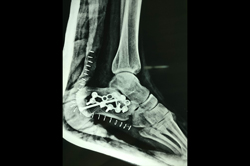

Calcaneum